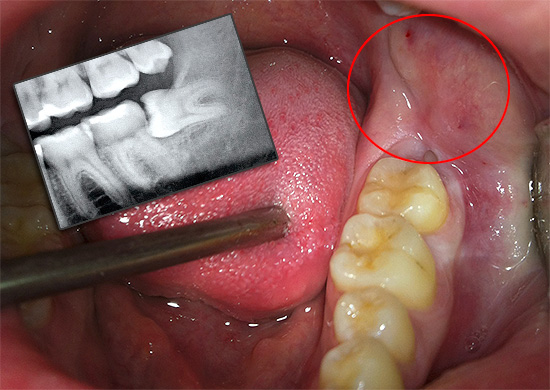

Pertanto, un forte dolore indica spesso un processo infiammatorio sotto il cosiddetto cappuccio gengivale - un tessuto molle sopra il dente che li danneggia.

Oltre al dolore, si notano gonfiore e arrossamento delle gengive. Nel tempo, le forme di pus sotto il cappuccio di un dente del giudizio, la temperatura può aumentare, si verifica spesso mal di testa, l'appetito diminuisce, la salute generale peggiora e appare debolezza. Durante la deglutizione, può verificarsi dolore sul lato in cui cresce il dente del giudizio, a volte la gola, l'orecchio e persino l'intera mascella fanno male.

Con un aumento della quantità di pus nell'area dell'infiammazione, l'apertura della bocca peggiora, il che a volte non consente al medico di esaminare completamente l'area corrispondente della gomma, che ha causato tali problemi. Il dolore e altri sintomi e segni ad esso associati consentono al dentista di fare una diagnosi: pericoronite o difficile dentizione della saggezza.

I linfonodi sottomandibolari si allargano e diventano dolorosi alla palpazione. Con la pressione sul cappuccio, il pus viene rilasciato - la causa di tutte le sofferenze. Sullo sfondo di un dente del giudizio in eruzione difficile, vengono visualizzati arrossamento e gonfiore del tessuto della guancia adiacente, arco palato-linguale e palato molle.